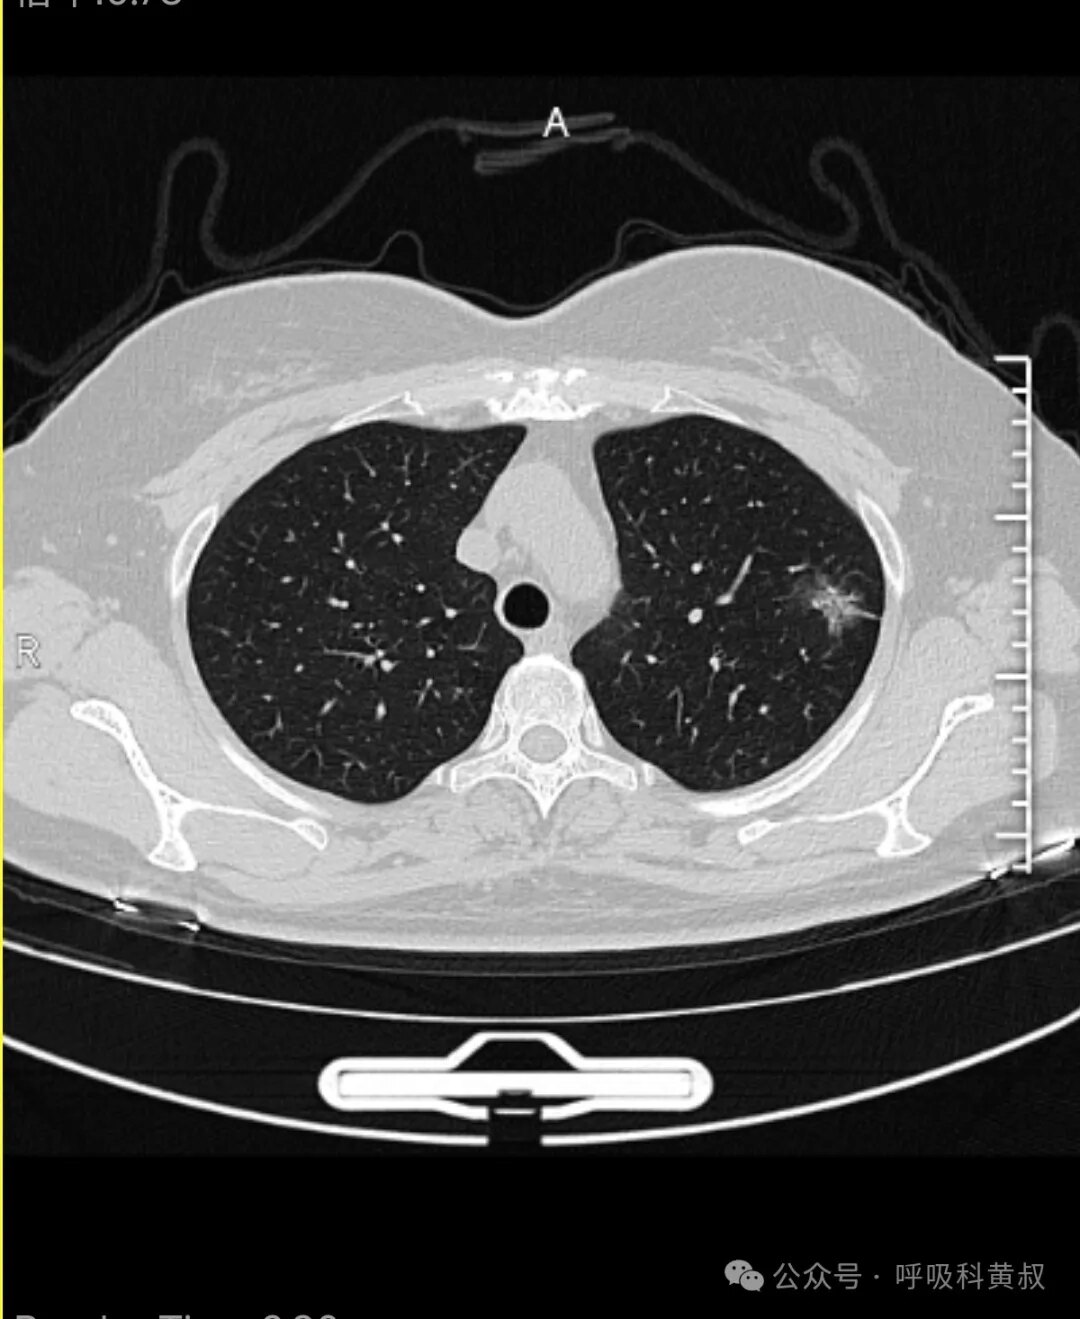

高齡男性患者,2021年發(fā)現(xiàn)左肺上葉腫塊,考慮肺癌,CT見(jiàn)下圖腫塊侵犯縱隔,行經(jīng)皮肺穿刺,病理提示鱗癌,PD-L140%。診斷明確,行免疫治療3個(gè)周期后家屬拒絕進(jìn)一步治療,三周期后CT如下圖腫瘤基本達(dá)到CR,治療效果非常好!后續(xù)患者未再次來(lái)院復(fù)查。近日門診,驚訝的發(fā)現(xiàn)患者來(lái)門診復(fù)診,主訴胸悶氣短(其有慢阻肺病史),遂復(fù)查胸部CT,結(jié)果如下其腫塊仍穩(wěn)定在四年前停藥時(shí)的狀態(tài),堪稱免疫治療的奇跡?。闹改系慕嵌葋?lái)說(shuō),PD-L1表達(dá)50%以上的鱗癌患者,可選擇單免疫治療。該患者PD-L1表達(dá)40%,當(dāng)時(shí)考慮其高齡,心肺功能差,選擇了單免疫治療,沒(méi)想到也達(dá)到了如此完美的效果。更多精彩科普及病例,可關(guān)注微信公眾號(hào)